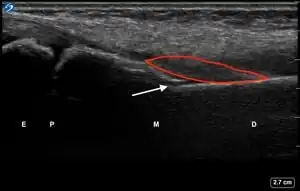

| Secondary Signs of Pediatric Distal Forearm Cortical Break Fractures | # | Sonographic Signs | Ultrasound Image |

| 4 | Pronator quadratus hematoma[17][14][18] | ![]() |

Ultrasound Scanning for Pronator Quadratus Hematoma Sign

While the patient has their affected forearm supinated at least 90 degrees, maintain the probe perpendicular to the skin, align the probe with the metaphysis of the distal radius, and increase the depth to 4 cm.

Record a 4 second video while slowly sweeping across the volar (palmar) aspect of the distal forearm until the metaphysis of the distal ulna is in the field of view.

Review the video to obtain an image of the largest section of the pronator quadratus muscle, which is typically the mid-portion of the sweep.

Repeat steps 1-3 with the unaffected forearm for comparison. Compare the thickness and appearance of the pronator quadratus muscle on both sides.

Note whether the affected forearm has a hematoma of the pronator quadratus muscle.